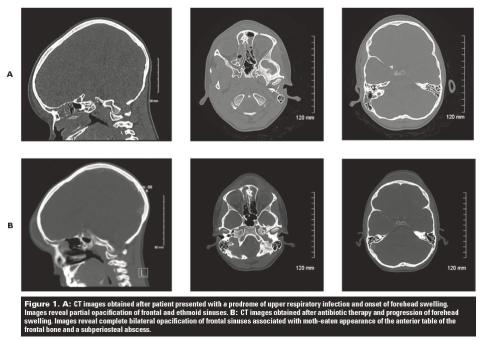

Forehead swelling in a 10-year-old male: A case report

Case data A 10-year-old boy presented to a regional hospital emergency department with forehead swelling 2 weeks after he had experienced 4 days of upper respiratory tract infection with symptoms of high fever,... Read More